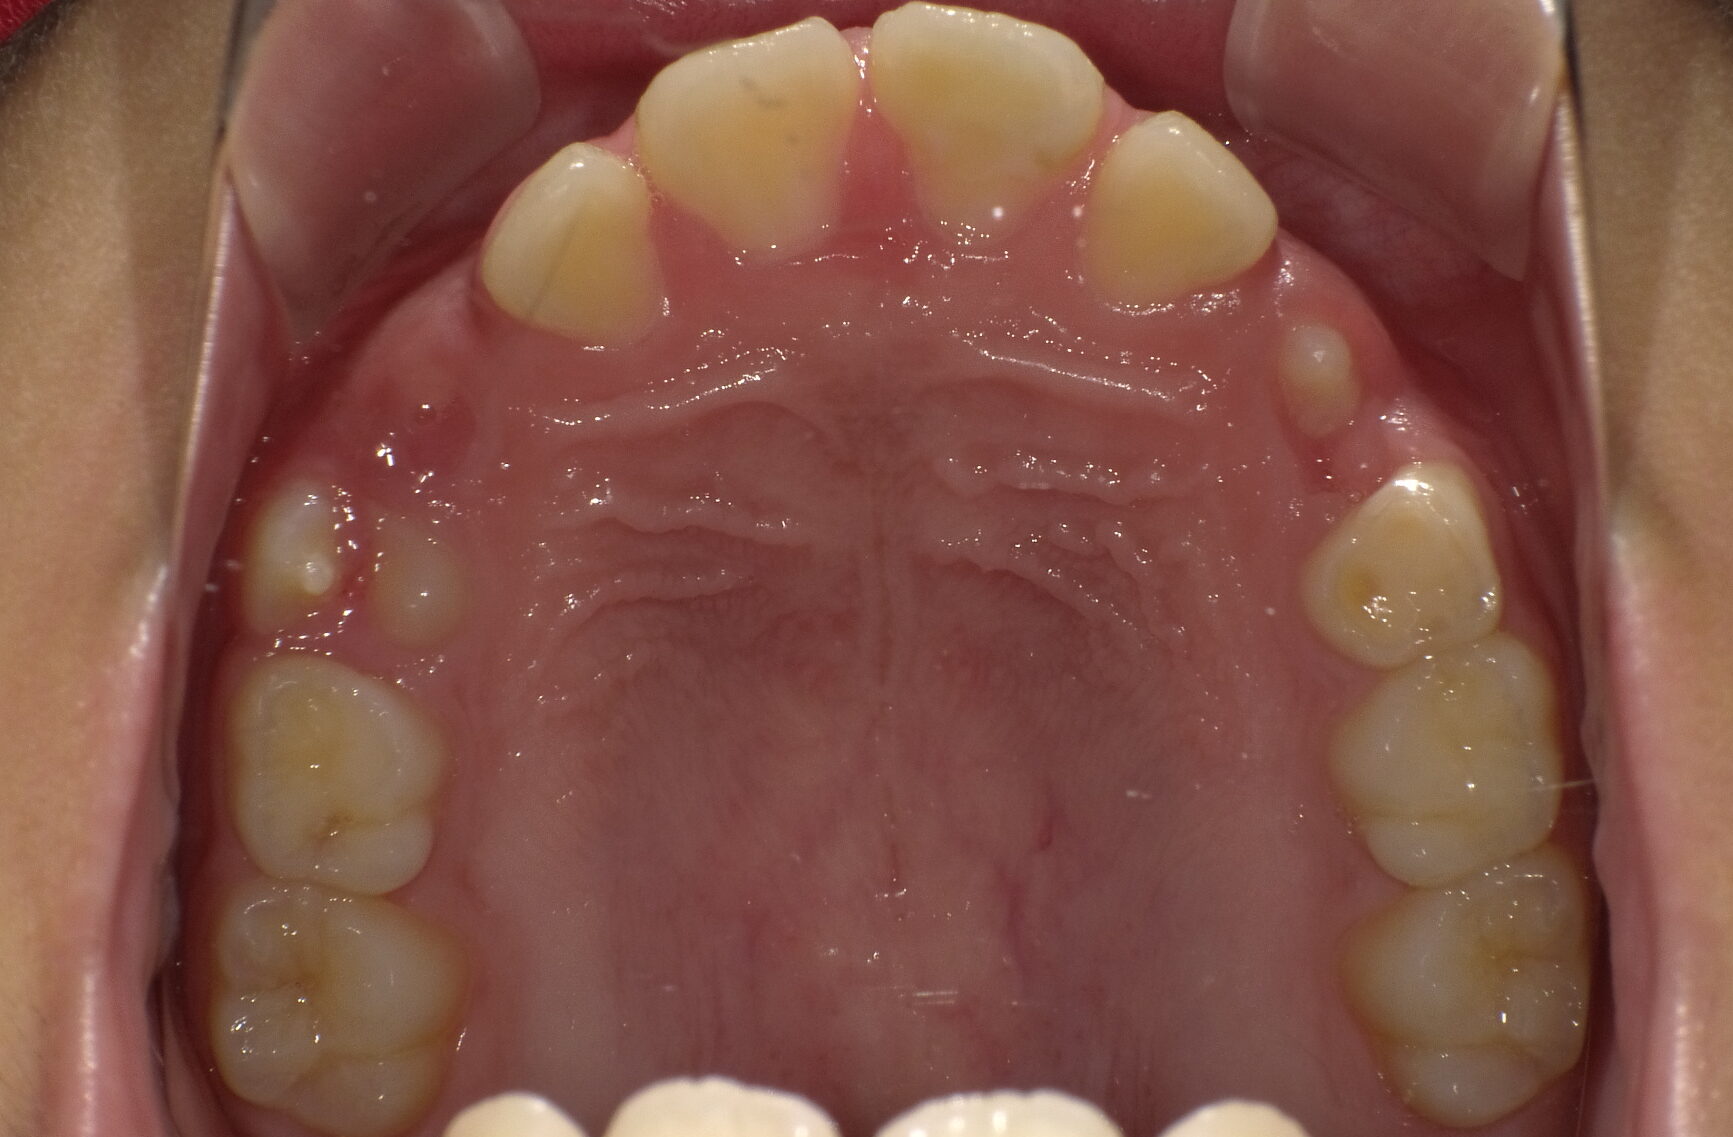

上下顎前突 10歳8ヶ月 男の子

治療前

骨格:上下あごともに前方に出やすい傾向(上下顎前突)

歯並び:前歯の前方への突出(出っ歯傾向)

成長を利用した1期治療にて、マウスピース型装置や矯正装置を用い、歯並びと口元のバランスの改善を行いました